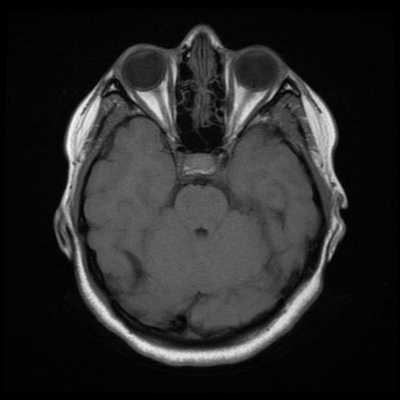

Как же узнать, есть ли на снимках признаки болезни? Самое главное - запомнить, как выглядит головной мозг здорового человека. Врач, изучая снимки пациентов, постоянно сравнивает их с нормальными снимками, хранящимися у него в голове. Чтобы понять, как это происходит - посмотрите на снимки внизу:

Перед вами - два снимка, сделанных в одном режиме. Снимок снизу - норма. Какое заболевание, в таком случае, есть на верхнем снимке? Чтобы понять это, нужно сравнить эти изображения. Явно видно отличие - на верхнем снимке в правой части головного мозга есть новообразование. Разница еще заметнее, если сравнить левую и правую части того же снимка.

Отметим его красной окружностью. Визуально оно представляет собой узел, неоднородный по окраске и отличающийся от серого и белого вещества головного мозга. В таких случаях, чтобы точно определить границы опухоли и определить её тип исследование повторяют с контрастом. Введение контрастного препарата в кровь через локтевую вену приводит к накоплению контрастного вещества в тканях опухоли - нормальные здоровые ткани его практически не накапливают. И мы получаем следующую картину, показанную на рисунке справа. Яркая окраска опухоли соответствует накопленному контрасту - теперь можно не только сказать, где опухоль, но и примерно определить, что это доброкачественная опухоль, так как она имеет четкие границы (злокачественные опухоли прорастают окружающие ткани, из-за чего границы будут размытыми и не такими четкими).